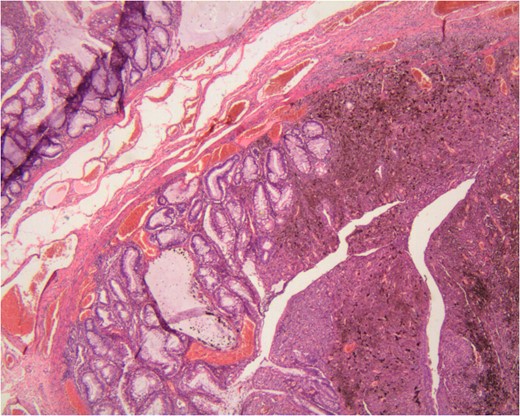

The histopathology reported a pedicle, mostly exophytic tumour of the anorectal junction, measuring 2.5 × 2.5 × 1.5 cm3. This tumour is associated to a tubulo-villous polyp in low grade dysplasia coexisting on the tumour pedicle. The tumour was of mixed histology, associating epithelioid and spindle cells. The superficial muscular layer was invaded. The nine lymph nodes examined and all resection margins were free of tumour. No perineural invasion was revealed. There was no BRAF mutation identified on genetic analysis.

The rarity of this case is based on the observation of a tubulo-vilous polype on the tumour pedicle. Actually there was a small in situ melanoma on the anal side that turn into a polypoid and invasive melanoma upwards to the rectal mucosa. It infiltrated the dysplastic polyp that was on its way. We can therefore call this a ‘collision tumour’. We do not know to this date if there is any association of those two tumours on the anorectal melanoma pathogenesis [6].